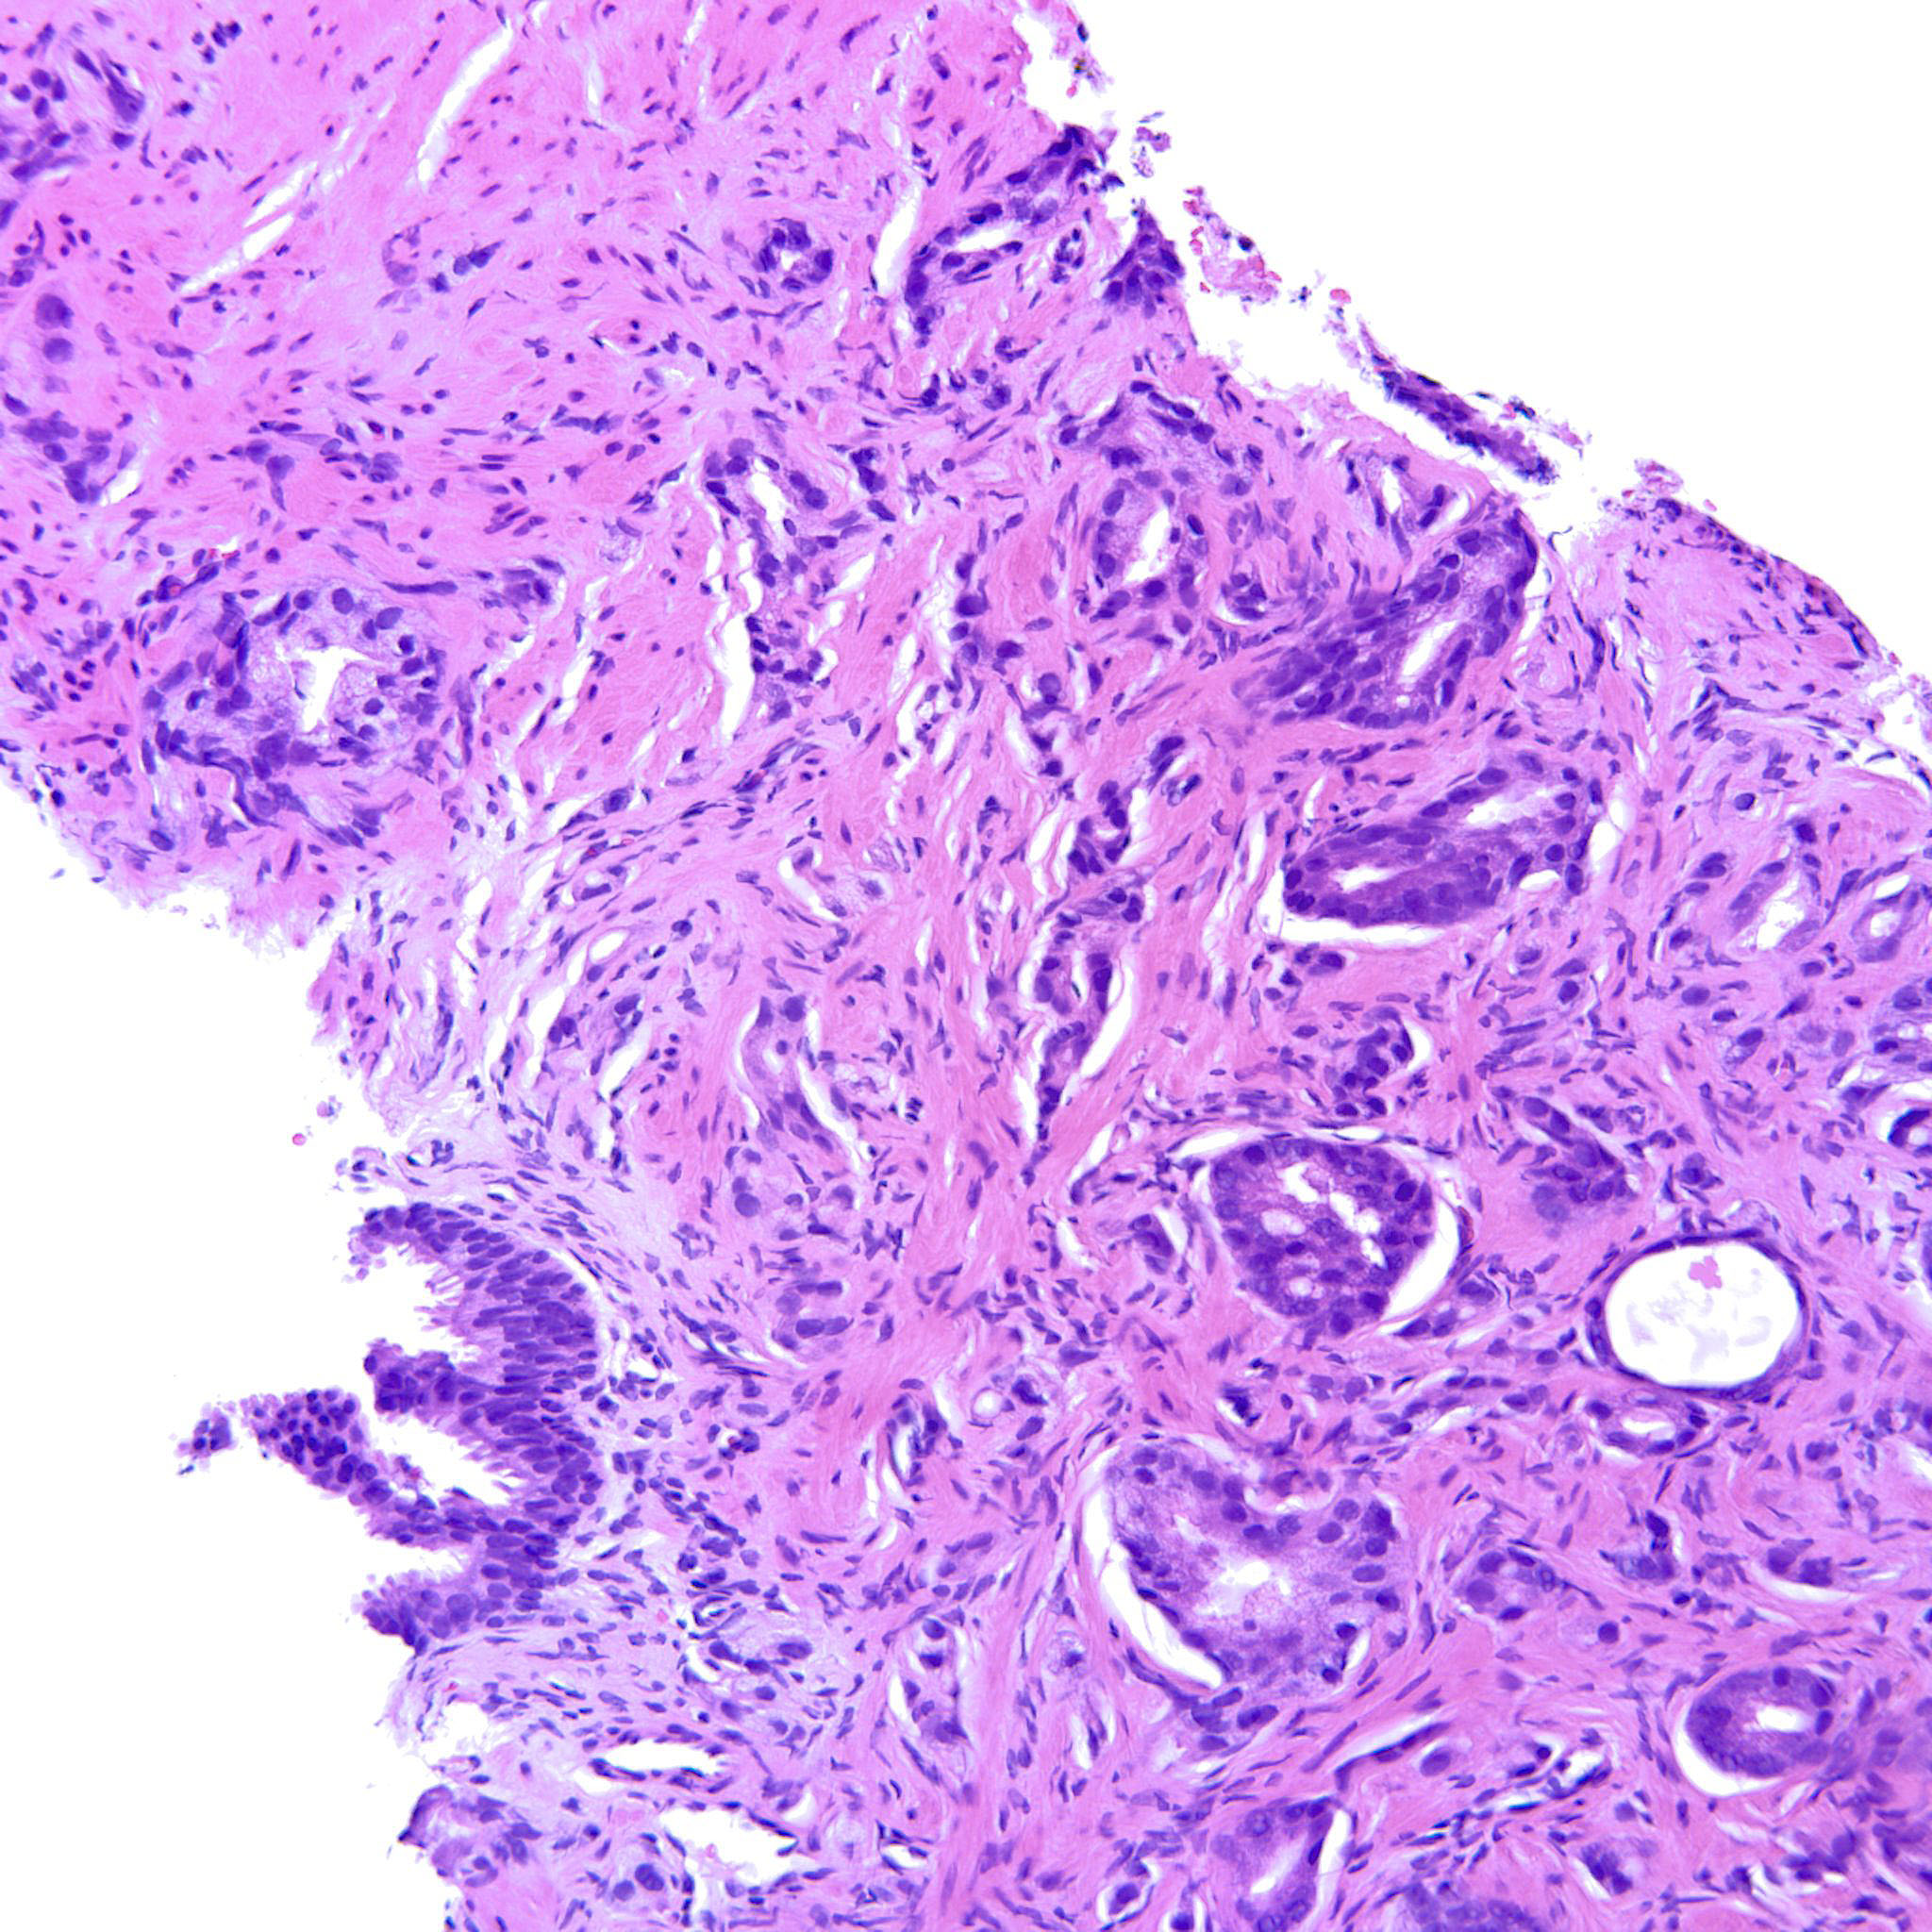

Prostate cancer grading

Case ID: 193